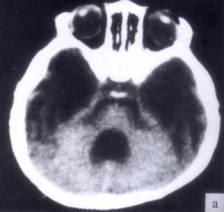

问题 病历摘要:??患者女性,10岁。结核性脑膜炎愈后8月,头痛伴恶心呕吐1周,并渐加重。体检:神清,精神差,反应迟钝,双眼底视神经乳头水肿,双眼外展差,余未见明显异常。 根据病史、CT,入院诊断考虑下列哪种?

选项 A.梗阻性脑积水 B.交通性脑积水 C.外部性脑积水 D.先天性脑积水 E.耳源性脑积水 F.良性颅内压增高 G.假性脑瘤

答案 B